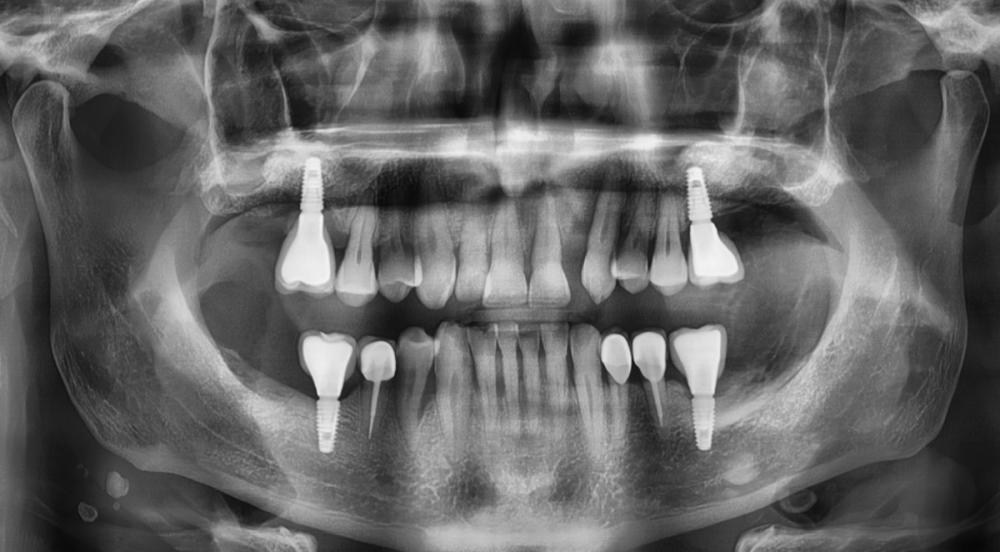

Irouil Опубликовано 8 августа, 2023 Автор Поделиться Опубликовано 8 августа, 2023 Ссылка на комментарий

АнтонТЛТ Опубликовано 8 августа, 2023 Поделиться Опубликовано 8 августа, 2023 Лучше прицельные снимки делать, на таких не рассмотреть ничего. Форум сильно сжимает изображение. Либо кадрировать эти снимки. Почему тибейсы такие короткие используются? Ссылка на комментарий

Irouil Опубликовано 9 августа, 2023 Автор Поделиться Опубликовано 9 августа, 2023 @АнтонТЛТ думаете короткие ти бейсы могут повлиять? Я сейчас не про пассивность. Лаба работает вообще с большим количеством нареканий, самое смешное в этом то, что она наша)) @NazranDantist согласен, есть риски, что какие-то сели внатяг. Ссылка на комментарий

АнтонТЛТ Опубликовано 9 августа, 2023 Поделиться Опубликовано 9 августа, 2023 Разве что короткие тибейсы могут упираться в ткани. Фдм какого диаметра используются на молярах? Ссылка на комментарий